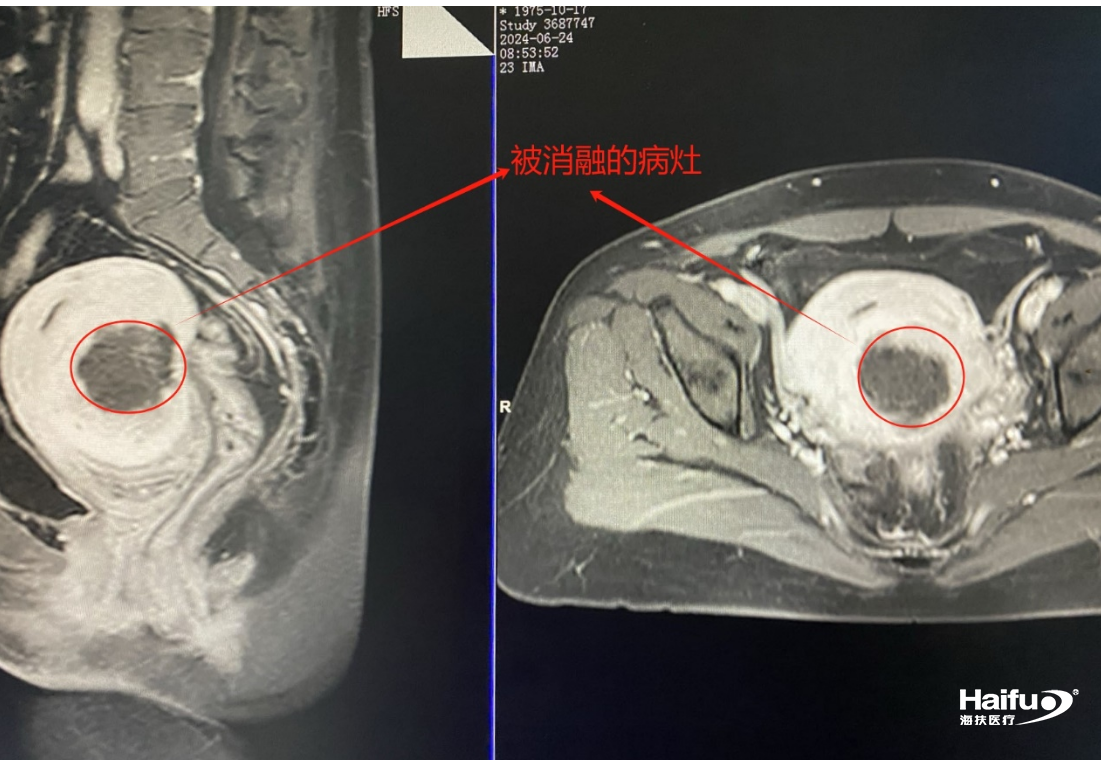

108976001719894049.png

HIFU消融治療術后MRI影像